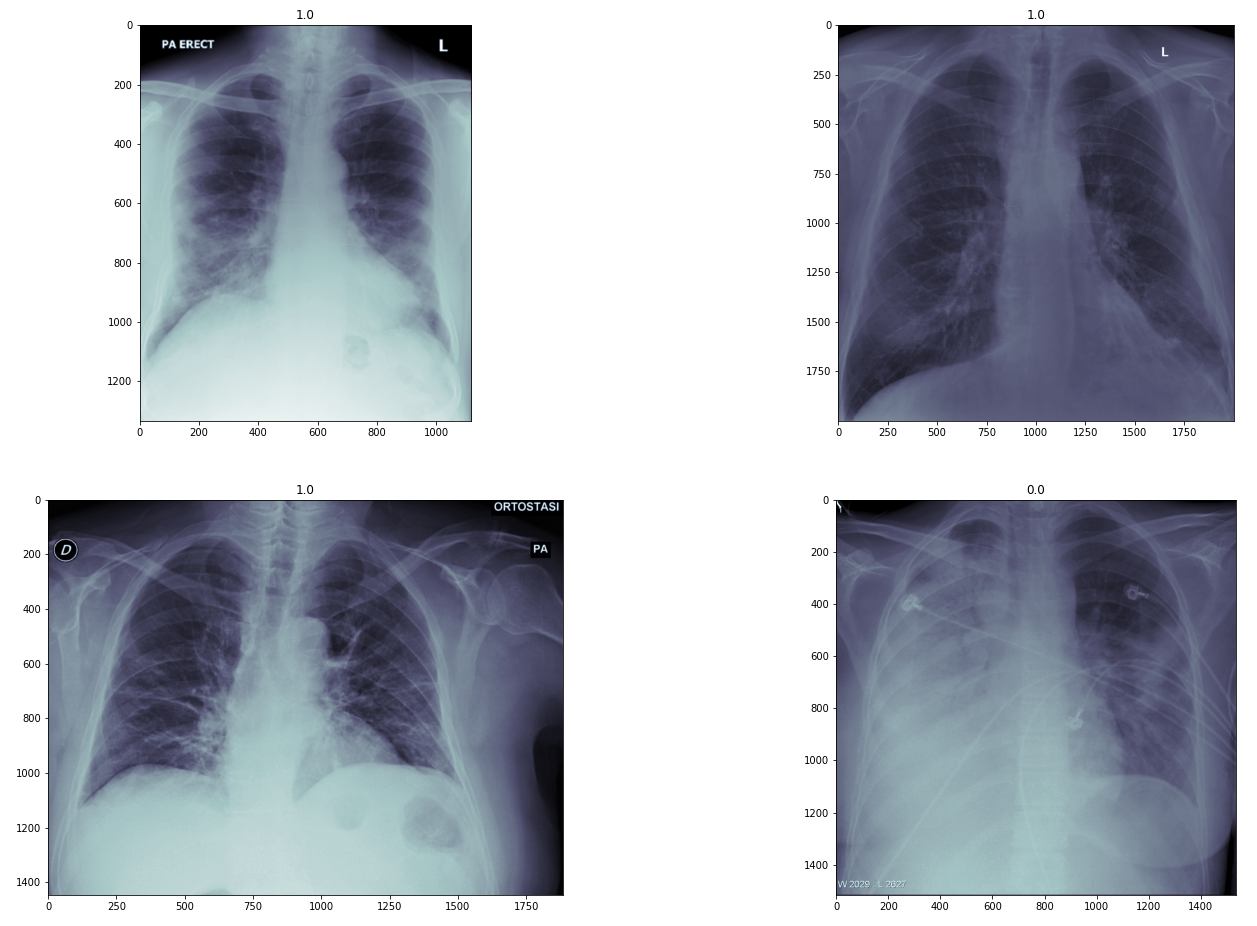

We use covid-chestxray-dataset [Cohen et al., 2020b] (Figure 1), an open dataset collected from public and indirect collection from hospitals and physicians. The dataset is available on GitHub. It has a total of 535 AP and PA view of X-ray images in PNG format, which is a lossless image format. The ratio of COVID-19 positive and negative is 63.9% and 36%, where total positive labels are 342 and non-positives are 193. The metadata of this dataset contains labels of 25 lungs disease, shown in Table 1. To avoid issues with float round off the image pixels are normalized to be in range of [-1024,1024].

Refer to caption

Figure 1: 1 means COVID-19 +Ve and 0 means -Ve.